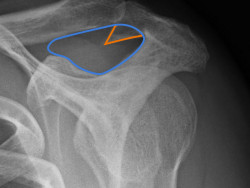

Die folgenden Röntgenbilder zeigen beispielhaft so einen Knochensporn, der die Sehne im Laufe der Jahre aufreibt:

Röntgenbilder der Schulter mit einem ausgeprägten Knochensporn: Rechts ist der Gleitraum der Rotatorenmanschette mit blau gekennzeichnet. Man kann erkennen, wie der orange eingezeichnete Sporn den Raum stark einengt.